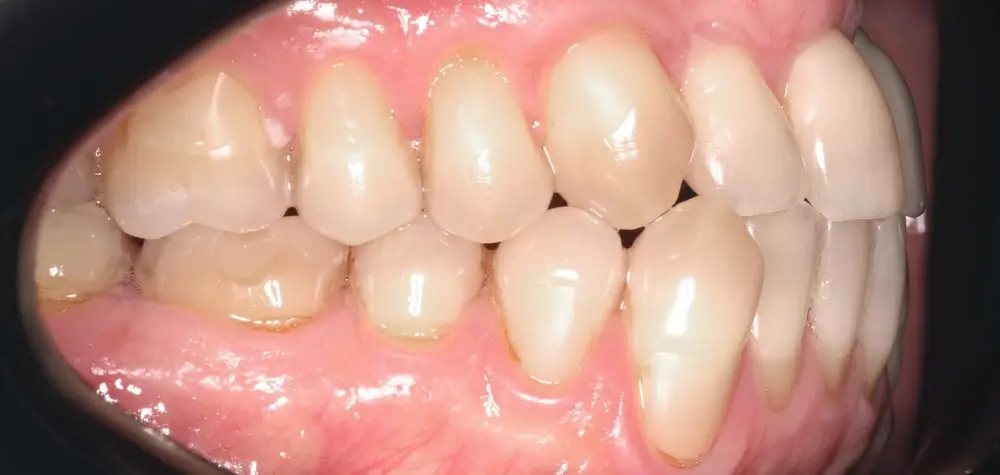

Мезиальный прикус - Кейс 7

Эффективность устранения дефекта прикуса посредством элайнеров FlexiLigner.

Результаты лечения